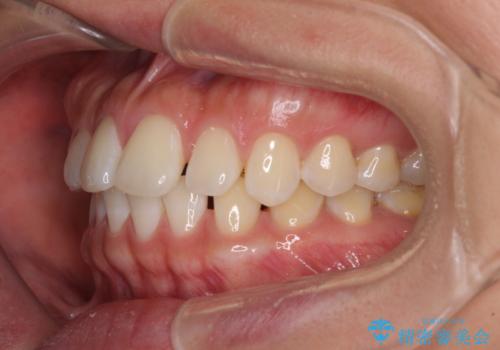

【モニター】前歯のすきっ歯をインビザラインで改善

- 上顎前歯の隙間と口元の突出感を気にして来院された患者様です。

高校生の時に行った矯正治療の後戻りであり、歯列不正は軽度であったので、インビザラインにて治療を行うこととしました。

すきっ歯はあっという間に後戻りを起こすので、可及的に後戻りを防止するために、上下前歯部を舌側からワイヤーで固定しています。

通常は下顎前歯のみに行っていますが、空隙歯列弓では上顎でも行っています。